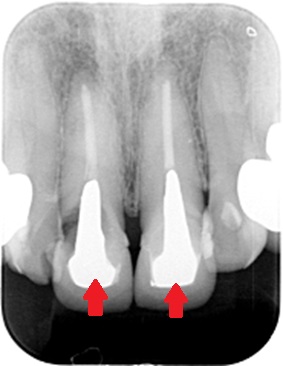

患者さんのレントゲン写真(エックス線検査)です。

太いメタルコア

赤い矢印が太いメタルコアが入っている歯です。歯の輪郭を線で書いてありますが、白く写るコアがめいっぱいに入っています。

青い矢印の歯にはスクリューポストというネジでコアが入っています。